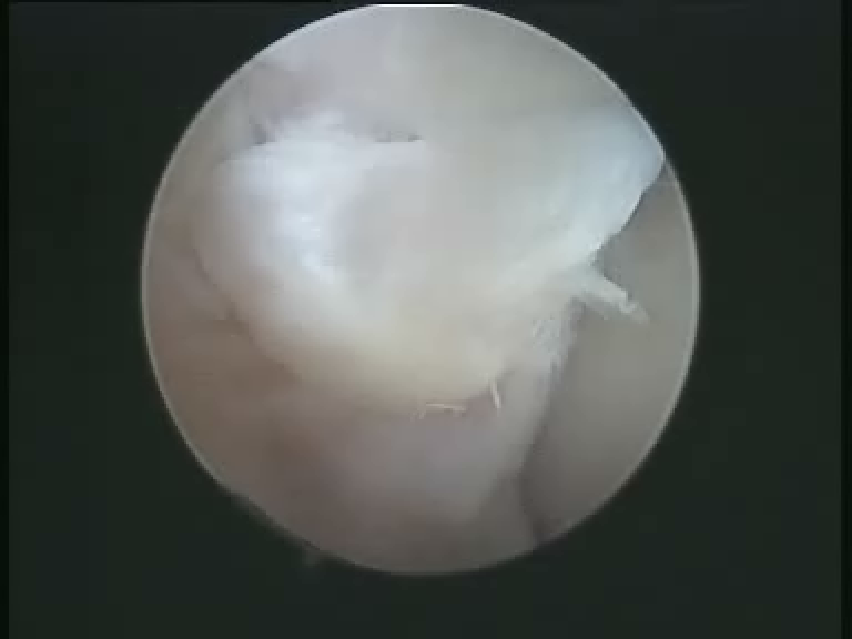

软骨剥脱